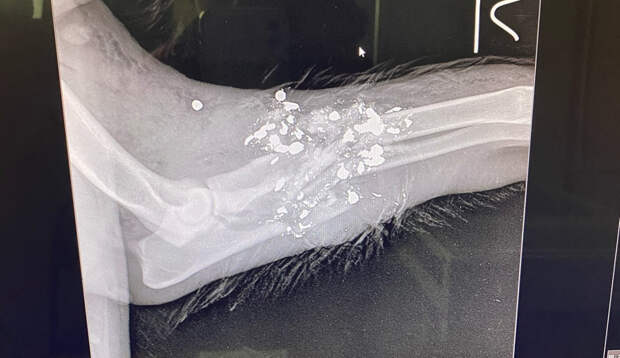

Уточняется, что неизвестные стрелки перемещаются на автомобиле и используют дробь.